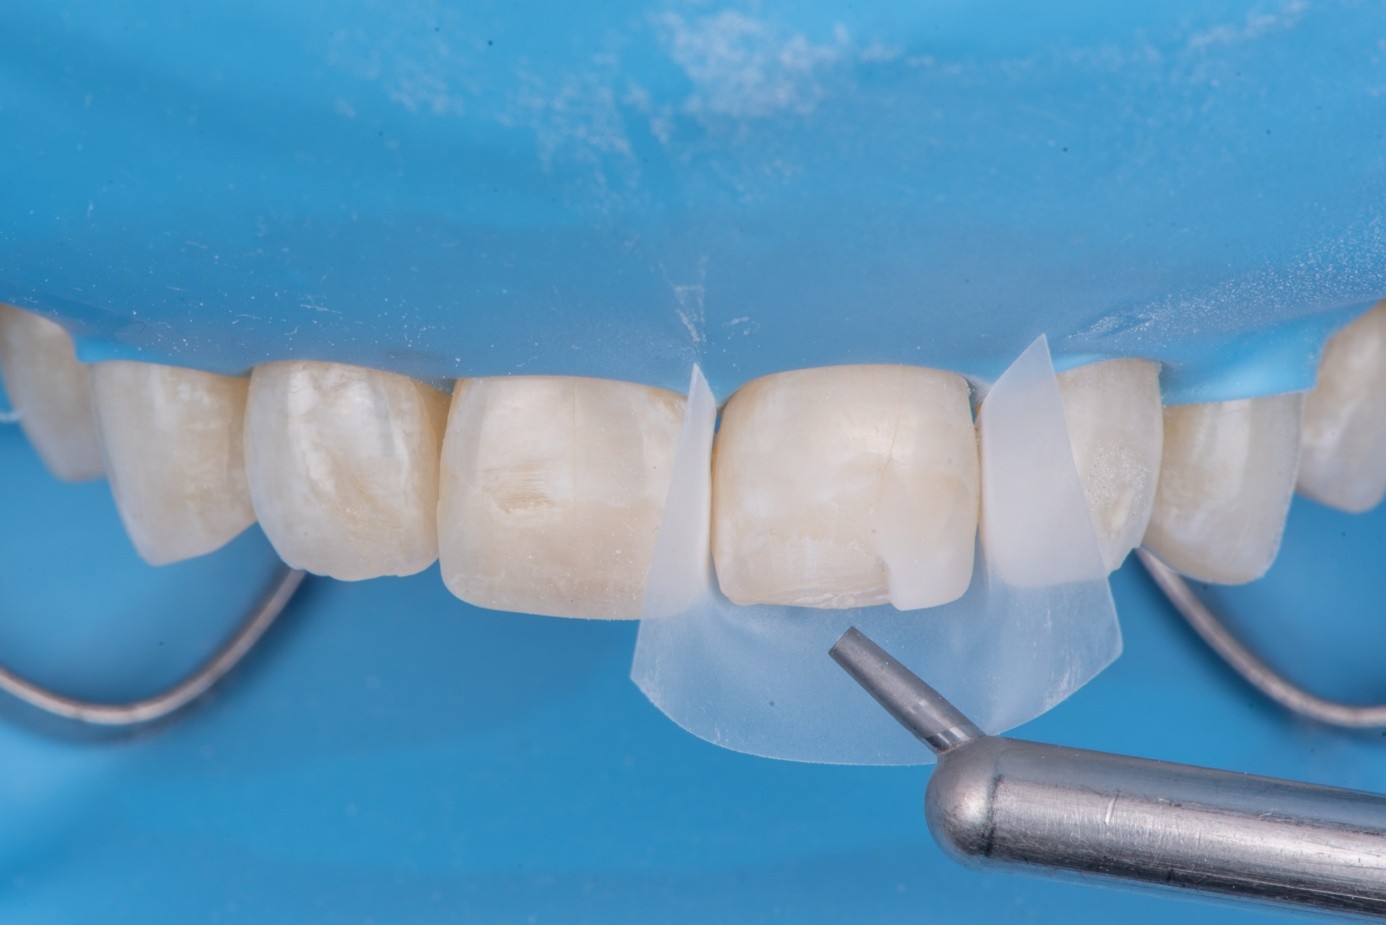

(14.) Intraoral view showing the fractured ceramic fragment positioned in place. The piece fits well, although minor gaps are present between the margins due to slight material loss, which can be restored using luting composite.

Figure 14

(15.) Intraoral view showing the fractured ceramic fragment positioned in place. The piece fits well, although minor gaps are present between the margins due to slight material loss, which can be restored using luting composite.

Figure 15

(16.) Intraoral view showing the fractured ceramic fragment positioned in place. The piece fits well, although minor gaps are present between the margins due to slight material loss, which can be restored using luting composite.

Figure 16